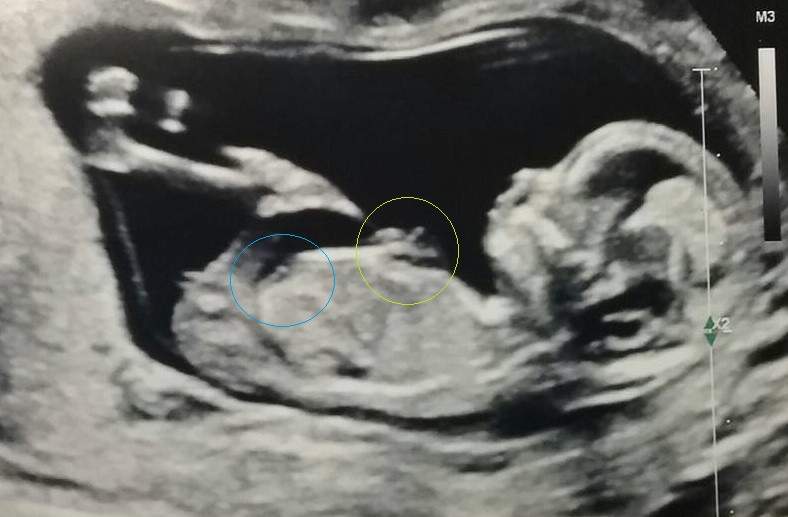

I'm not sure if what I'm seeing is a boy nub between the legs or a finger. It looks just like the two fingers by its tummy. The technician didn't say anything. It was done at 13 weeks. Thanks for your help!